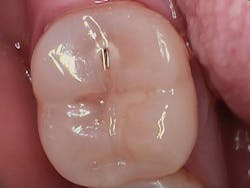

Figure 1 shows a large radiolucency on the mesial and a small radiolucency on the occlusal of tooth 31. Figure 2 shows an initial caries lesion on the distal pit and a leaking occlusal composite. Tooth 31 was sensitive to cold but normal to chewing, bite, and heat. Selective caries removal was used to prevent pulp exposure and preserve the marginal ridge.

Figure 3 shows the final restoration immediately after placement. Figure 4 shows the final restoration of an initial caries lesion on the buccal. The clinician anticipated maturation of the glass-hybrid in choosing a lighter shade of A2, which initially appeared much too light. A slightly darker shade may have been more appropriate.